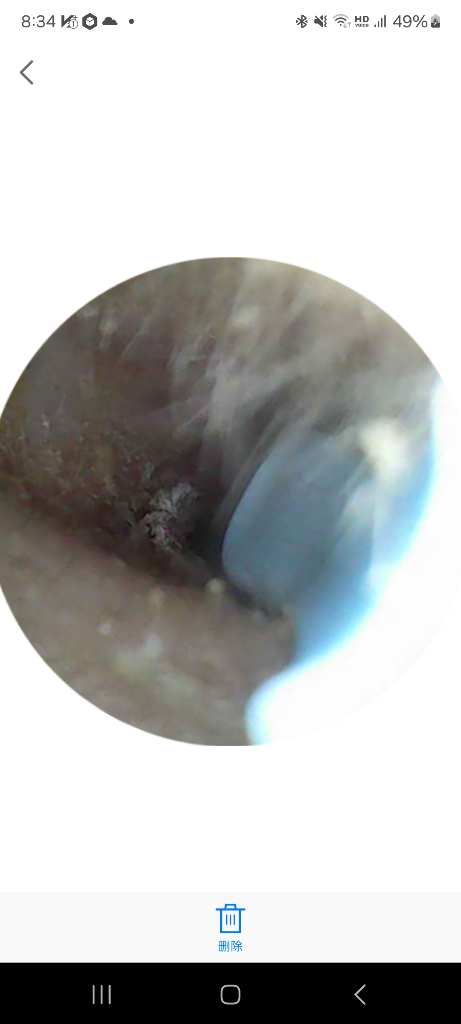

그래서 귀내시경사서 봤는데

빨갛고 뭔가 하얀개 딱지인지 뭔지 지저분하게

생겼습니다

올려주신 내시경사진의 경우는 가져져 있어서 구별이 잘 되지를 않네요